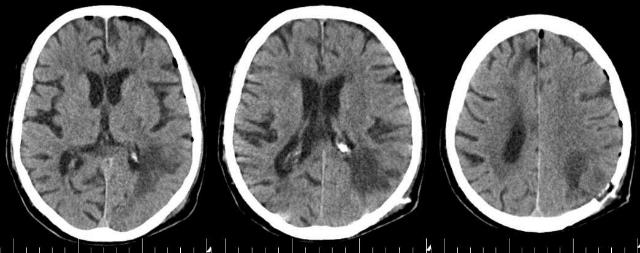

Инсульт удаление гематомы

Инсульт удаление гематомы 108 фотографий